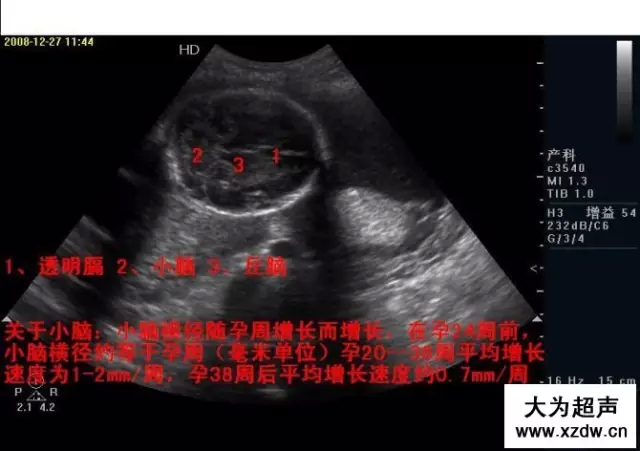

產(chǎn)科超聲正常圖片